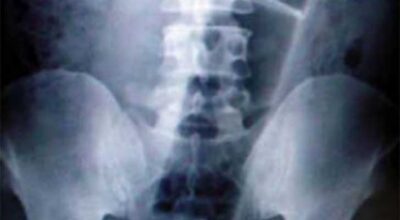

Esta recopilación de imágenes recoge alguna de las situaciones más estrambóticas que se han podido dar en una sala de rayos X. Todas ellas tienen algo en común: Son objetos extraños para el cuerpo humano que, de alguna manera han encontrado una vía de entrada, pero se han perdido a la hora de encontrar la de salida.

Muñecas de juguete descabezadas, botellas, armas, frascos, botes de plástico, teléfonos y hasta una cinta de casete pueden encontrarse en esa suerte de “punto limpio” al que ha quedado reducido el interior de los afectados.

No sabemos, ni juzgamos, la forma o los motivos por los que terminaron atrapados en dichas partes del cuerpo, pero estamos convencidos de que algún doctor estuvo al borde de la carcajada cuando se encontró con casos tan llamativos e inverosímiles como estos ¡Ver para creer!